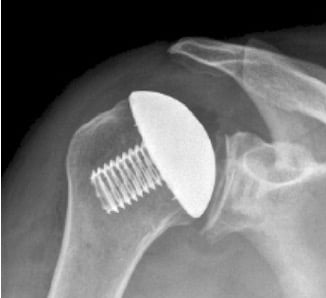

- Αρθροπλαστική: περιλαμβάνει την αντικατάσταση των φθαρμένων οστικών επιφανειών με μεταλλικές προθέσεις. Η αρθροπλαστική ενδείκνυται στις περιπτώσεις που η συντηρητική θεραπεία έχει αποτύχει και συμβάλλει στην ελαχιστοποίηση του πόνου και στην αύξηση του εύρους κίνησης του ώμου. Η επέμβαση πραγματοποιείται με συνδυασμό γενικής και περιοχικής αναισθησίας και απαιτεί συνήθως νοσηλεία μίας ημέρας. Υπάρχουν 2 κύριοι τύποι αρθροπλαστικής ώμου. Η Ανατομική Αρθροπλαστική Ώμου περιλαμβάνει την αντικατάσταση της κεφαλής του βραχιονίου με μεταλλική πρόθεση και την αντικατάσταση της ωμογλήνης με πλαστική πρόθεση. Η ανατομική αρθροπλαστική γίνεται σε νεότερους ασθενείς με ακέραιο στροφικό πέταλο. Η Ανάστροφη Αρθροπλαστική Ώμου πραγματοποιείται σε ασθενείς με σημαντικές ρήξεις στροφικού πετάλου και σε μεγαλύτερους σε ηλικία ασθενείς. Στην ανάστροφη αρθροπλαστική, η κεφαλή και η κοίλη επιφάνεια («κούπα») τοποθετούνται αντίστροφα από το φυσιολογικό (κοίλη επιφάνεια στην κεφαλή του βραχιονίου και γληνόσφαιρα στην ωμογλήνη). Η επέμβαση είναι πολύ επιτυχημένη και έχει γίνει εξαιρετικά δημοφιλής παγκοσμίως τα τελευταία χρόνια, με τα αποτελέσματα να είναι πολύ ενθαρρυντικά.